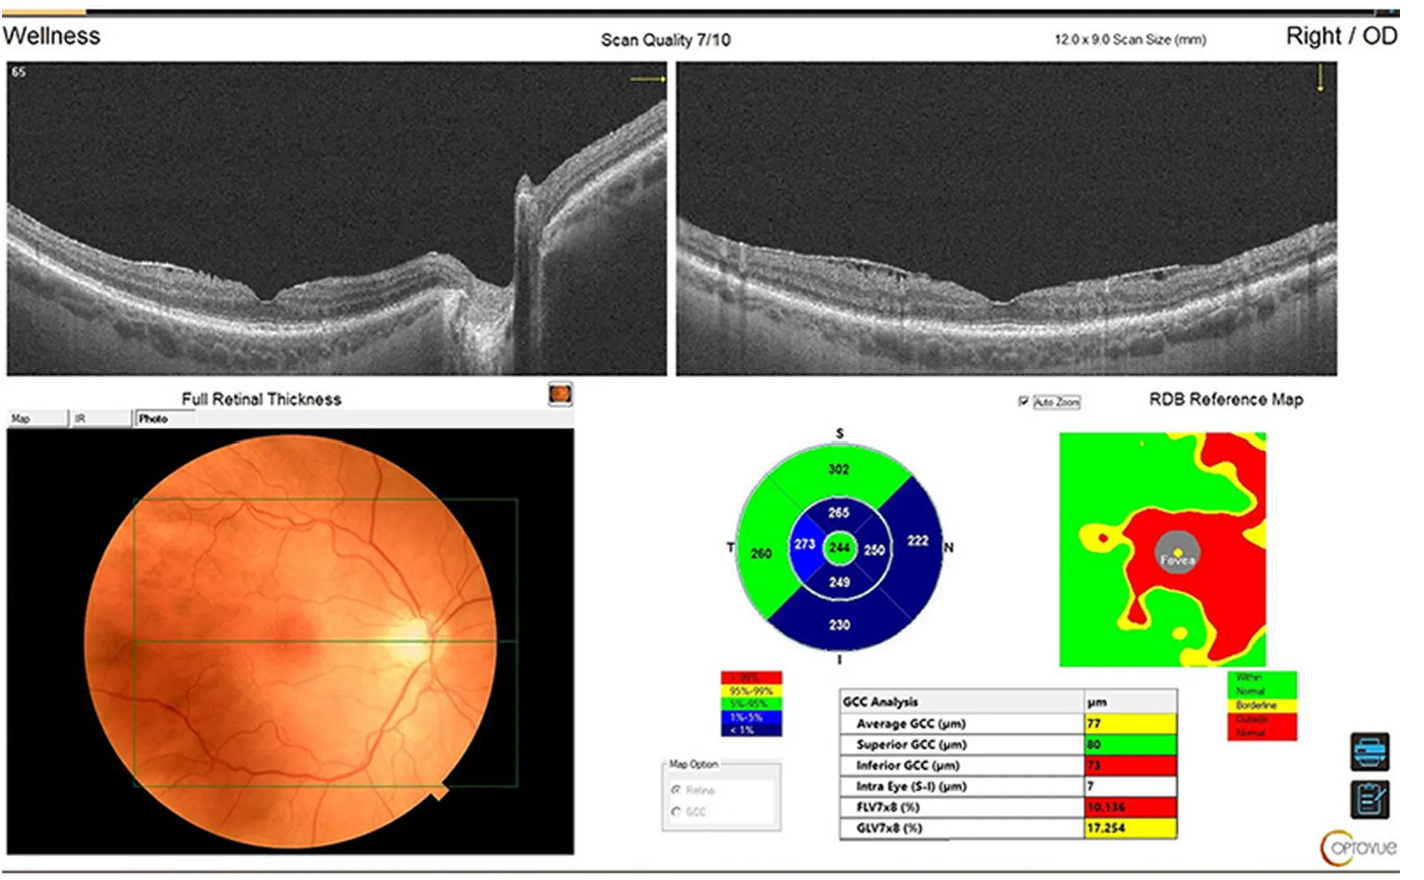

Оптический когерентный томограф Optovue Solix обладает повышенной скоростью сканирования — 120 000 А-сканов в секунду. SOLIX предоставляет множество инструментов для нового поколения борьбы с заболеваниями, которые повышают пропускную способность и обеспечивают превосходный уход за пациентами. В отличие от томографов более ранних поколений ОКТ SOLIX OPTOVUЕ может определять наличие конкрементов и новообразований сосудов сетчатки и хориоидеи, позволяет получать максимально точную послойную визуализацию структур глаза.

- Программа AngioAnaliticsTM для количественного анализа сосудов сетчатки;